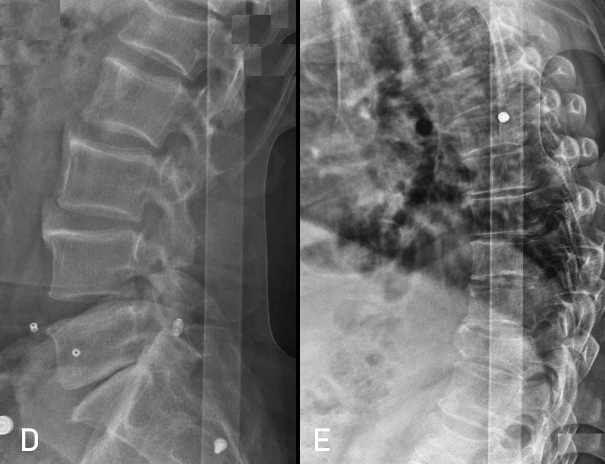

Kırık bulunan diğer vertebralar olan T2,T3,T4,T6 ve L5 vertebralarına işem uygulanmadı, takibe alındı.

Hasta cerrahinin ertesi sabahı TLSO ile sorunsuz olarak moblize edildi

ve postop ikinci gün taburcu edildi. Kısa dönem takipte bir sorunu

yoktur.